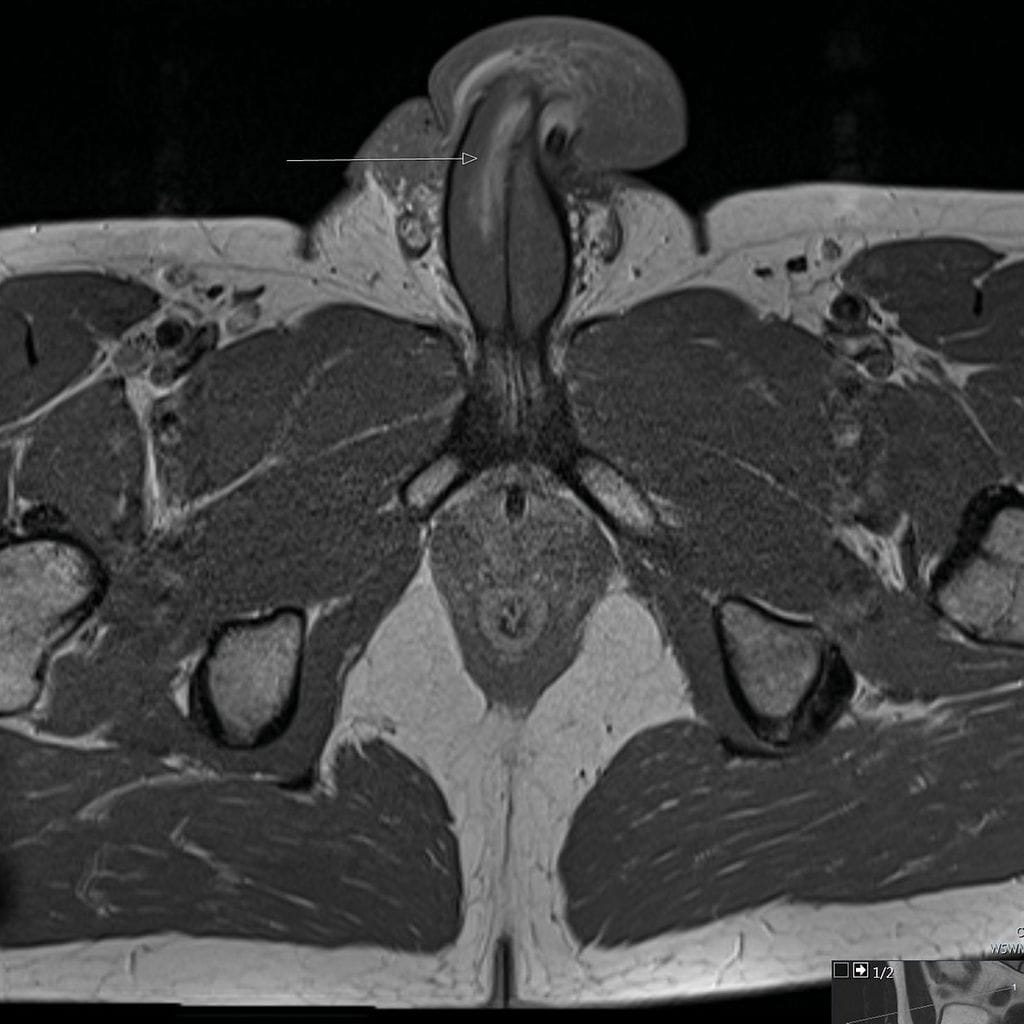

Magneettikuvaus kuitenkin paljasti, että siittimen paisuvaiskudosta ympäröivä valkokalvo oli repeytynyt. Peniksessä oli kolmen senttimetrin mittainen pituussuuntainen repeämä.